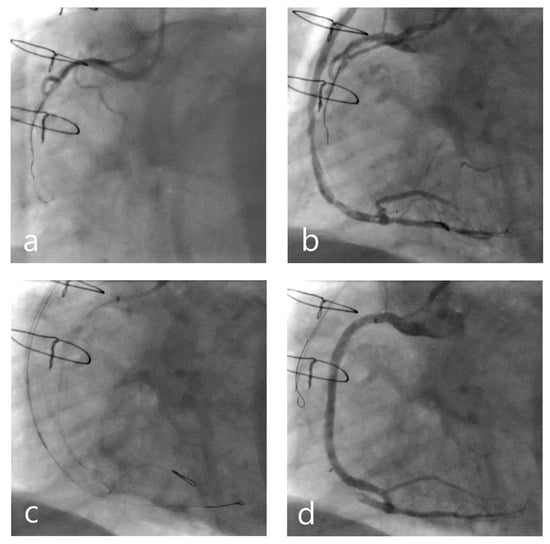

- Wilson, S.J.; Hanratty, C.G.; Spence, M.S.; Owens, C.G.; Rigger, J.; Spratt, J.C.; Walsh, S.J. Saphenous Vein Graft Sacrifice Following Native Vessel PCI is Safe and Associated with Favourable Longer-Term Outcomes. Cardiovasc. Revascularization Med. 2019, 20, 1048–1052. [Google Scholar] [CrossRef]